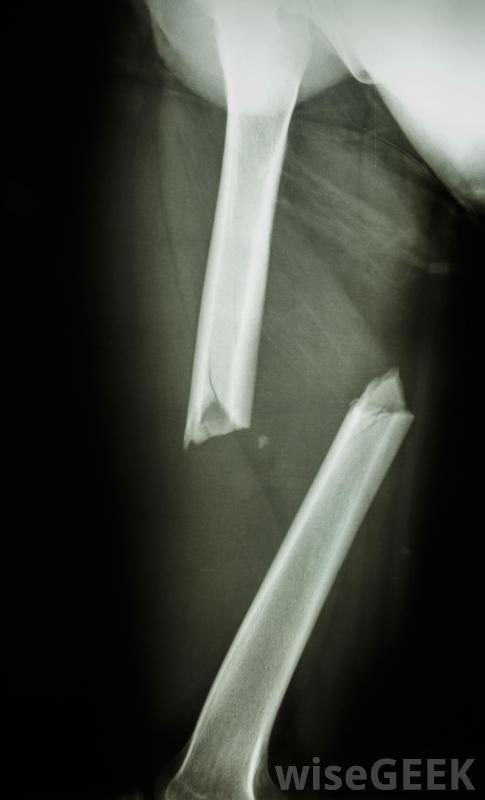

撞擊性骨折,當一塊骨頭碎裂,碎片被打入其他骨塊,可能是相當嚴重的,一旦確定損傷程度,應迅速治療,以避免進一步的問題。如果損傷不太嚴重,石膏、夾板或吊索可能足以將受傷的骨頭固定在適當的位置,以便愈合是的。更大范圍的骨折...

撞擊性骨折,當一塊骨頭碎裂,碎片被打入其他骨塊,可能是相當嚴重的,一旦確定損傷程度,應迅速治療,以避免進一步的問題。如果損傷不太嚴重,石膏、夾板或吊索可能足以將受傷的骨頭固定在適當的位置,以便愈合是的。更大范圍的骨折伴有多個骨碎片,可能需要手術將其復位,可能需要螺釘或銷釘之類的硬件將其固定。由于此類骨折通常非常痛苦,在愈合過程中可能需要藥物來控制它。

X光片將顯示骨骼骨折的嚴重程度。